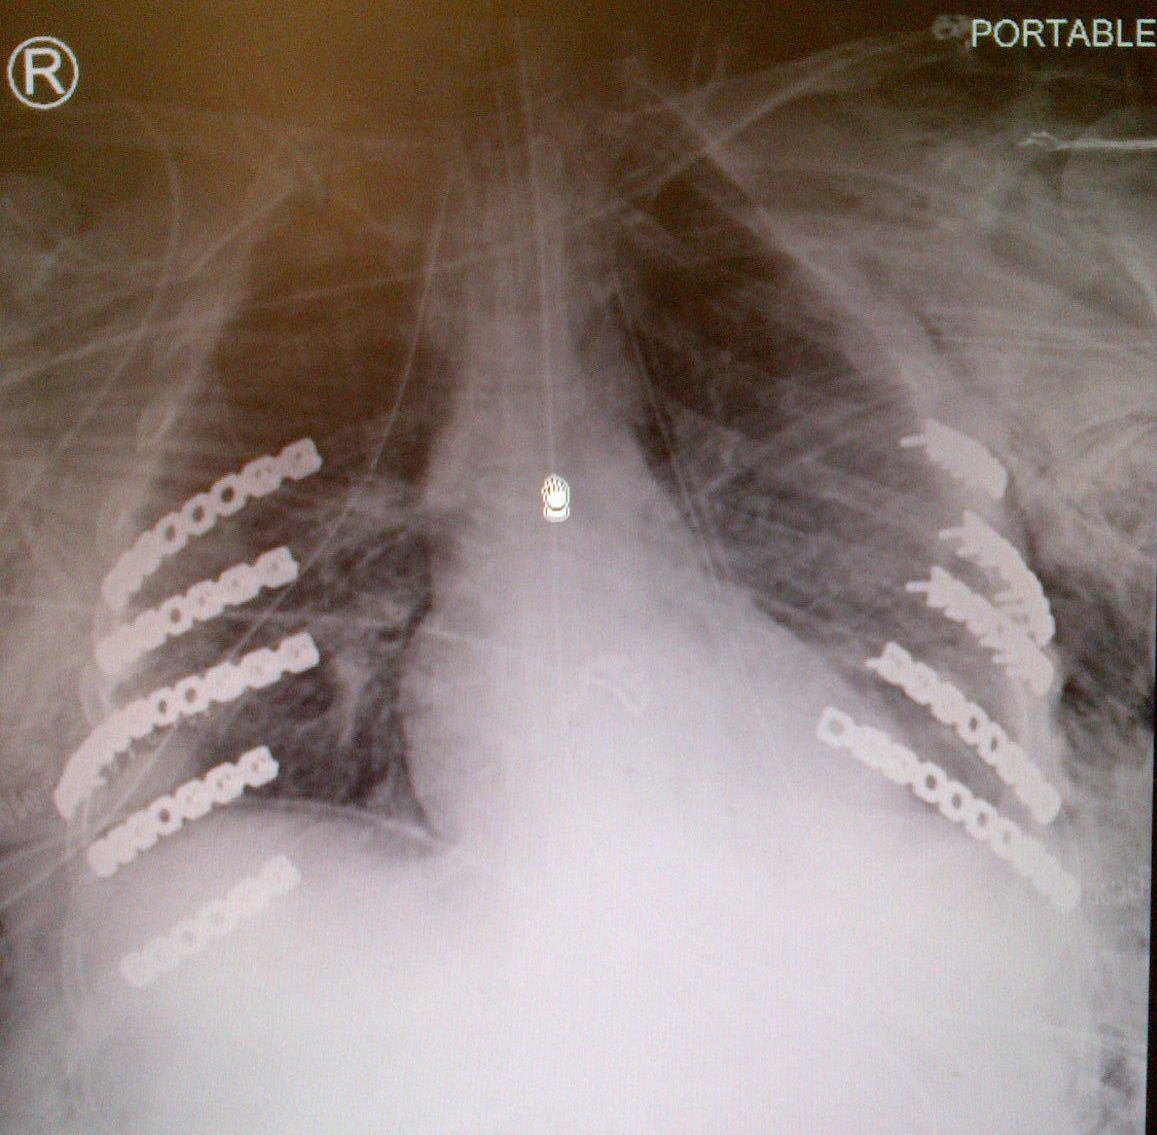

Surgical Fixation

Swart et al J Orthop Trauma 2017

- meta-analysis of surgical fixation

- decreased mortality

- decrease mechanical ventilation times

- decreased ICU and hospital sty

- decreased rates of pneumonia and tracheostomy